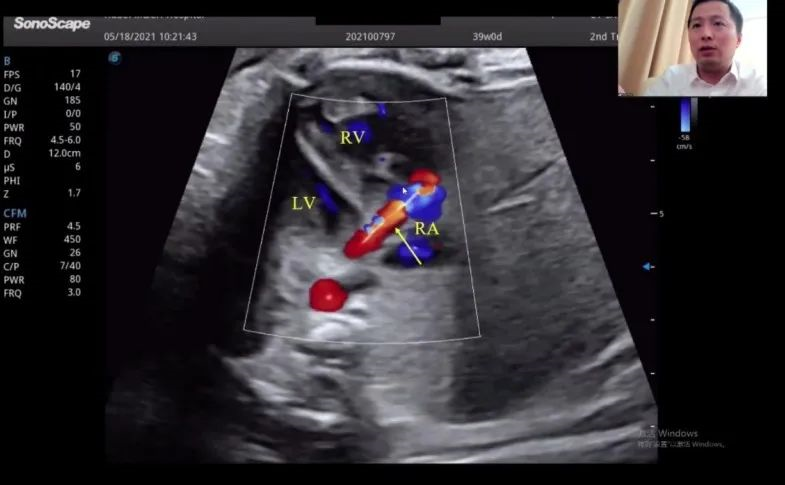

浙江大學(xué)醫(yī)學(xué)院附屬邵逸夫醫(yī)院的趙博文教授聚焦先天性心臟疾?。–HD)的產(chǎn)前診斷,通過(guò)特殊病例的展示講解,包括法洛四聯(lián)癥(TOF,一種常見(jiàn)的先天性心臟畸形)的時(shí)空關(guān)聯(lián)成像技術(shù)(Spatio-Temporal Image Correlation,STIC)、大動(dòng)脈完全轉(zhuǎn)位(cTGA)和右心室雙出口(DORV)的圖像,前瞻性地提出智能胎心的應(yīng)用場(chǎng)景。“胎心檢查人工智能的應(yīng)用非常有價(jià)值,能夠縮短檢查時(shí)間,提高臨床的診療效率,”趙教授如是說(shuō)。

湖北省婦幼保健院的趙勝教授在會(huì)上帶來(lái)了胎兒冠狀動(dòng)脈瘺超聲診斷研究的分享。趙教授表示,冠狀動(dòng)脈瘺在妊娠晚期可通過(guò)超聲檢查顯示出來(lái),經(jīng)線圈栓塞或冠狀動(dòng)脈瘺術(shù)后,進(jìn)一步的臨床過(guò)程通常較為順利。